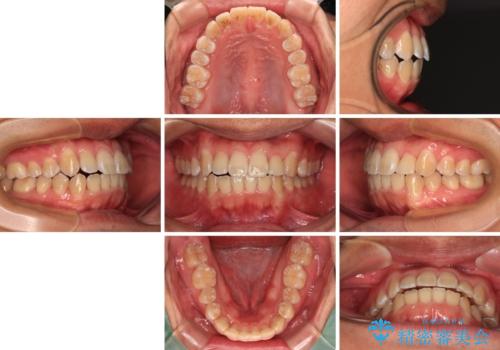

前歯のデコボコを費用を抑えたメタルブラケットできれいに

- 前歯のデコボコを気にして来院された患者様です。

極力費用を抑えた上で、自己管理の煩わしの少ない装置を希望とのことで、メタルブラケットによるワイヤー矯正を選択されました。

舌の突出癖があり、デコボコが解消される際に出っ歯傾向になる恐れがあるため、舌のトレーニングを行っていただきながら、矯正治療を進めていくこととしました。

治療終了直後は上下前歯が接触していましたが、舌の突出癖がなかなか改善されず、終了時の口腔内写真撮影時には、既に上下前歯に隙間ができてしまいました。